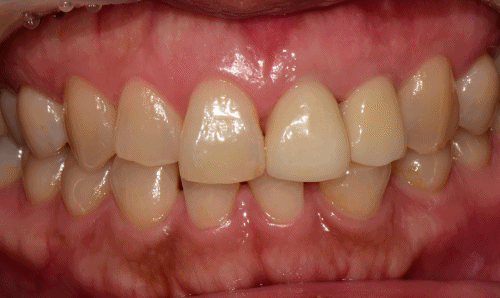

다시 3개월 후 보철을 완성해 드렸습니다.